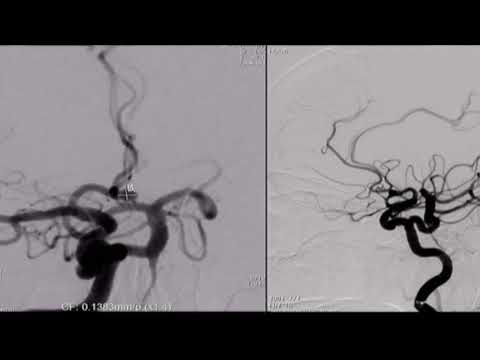

Hellow guys, Welcome to my website, and you are watching Anterior Choroidal Artery Management During Clipping of a Ruptured PCoA Aneurysm. and this vIdeo is uploaded by Barrow Neurological Institute at 2022-02-01T14:19:08-08:00. We are pramote this video only for entertainment and educational perpose only. So, I hop you like our website.